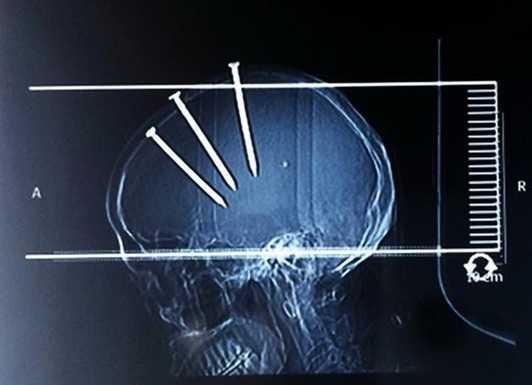

| Ảnh chụp X-quang phần đầu của bệnh nhân. |